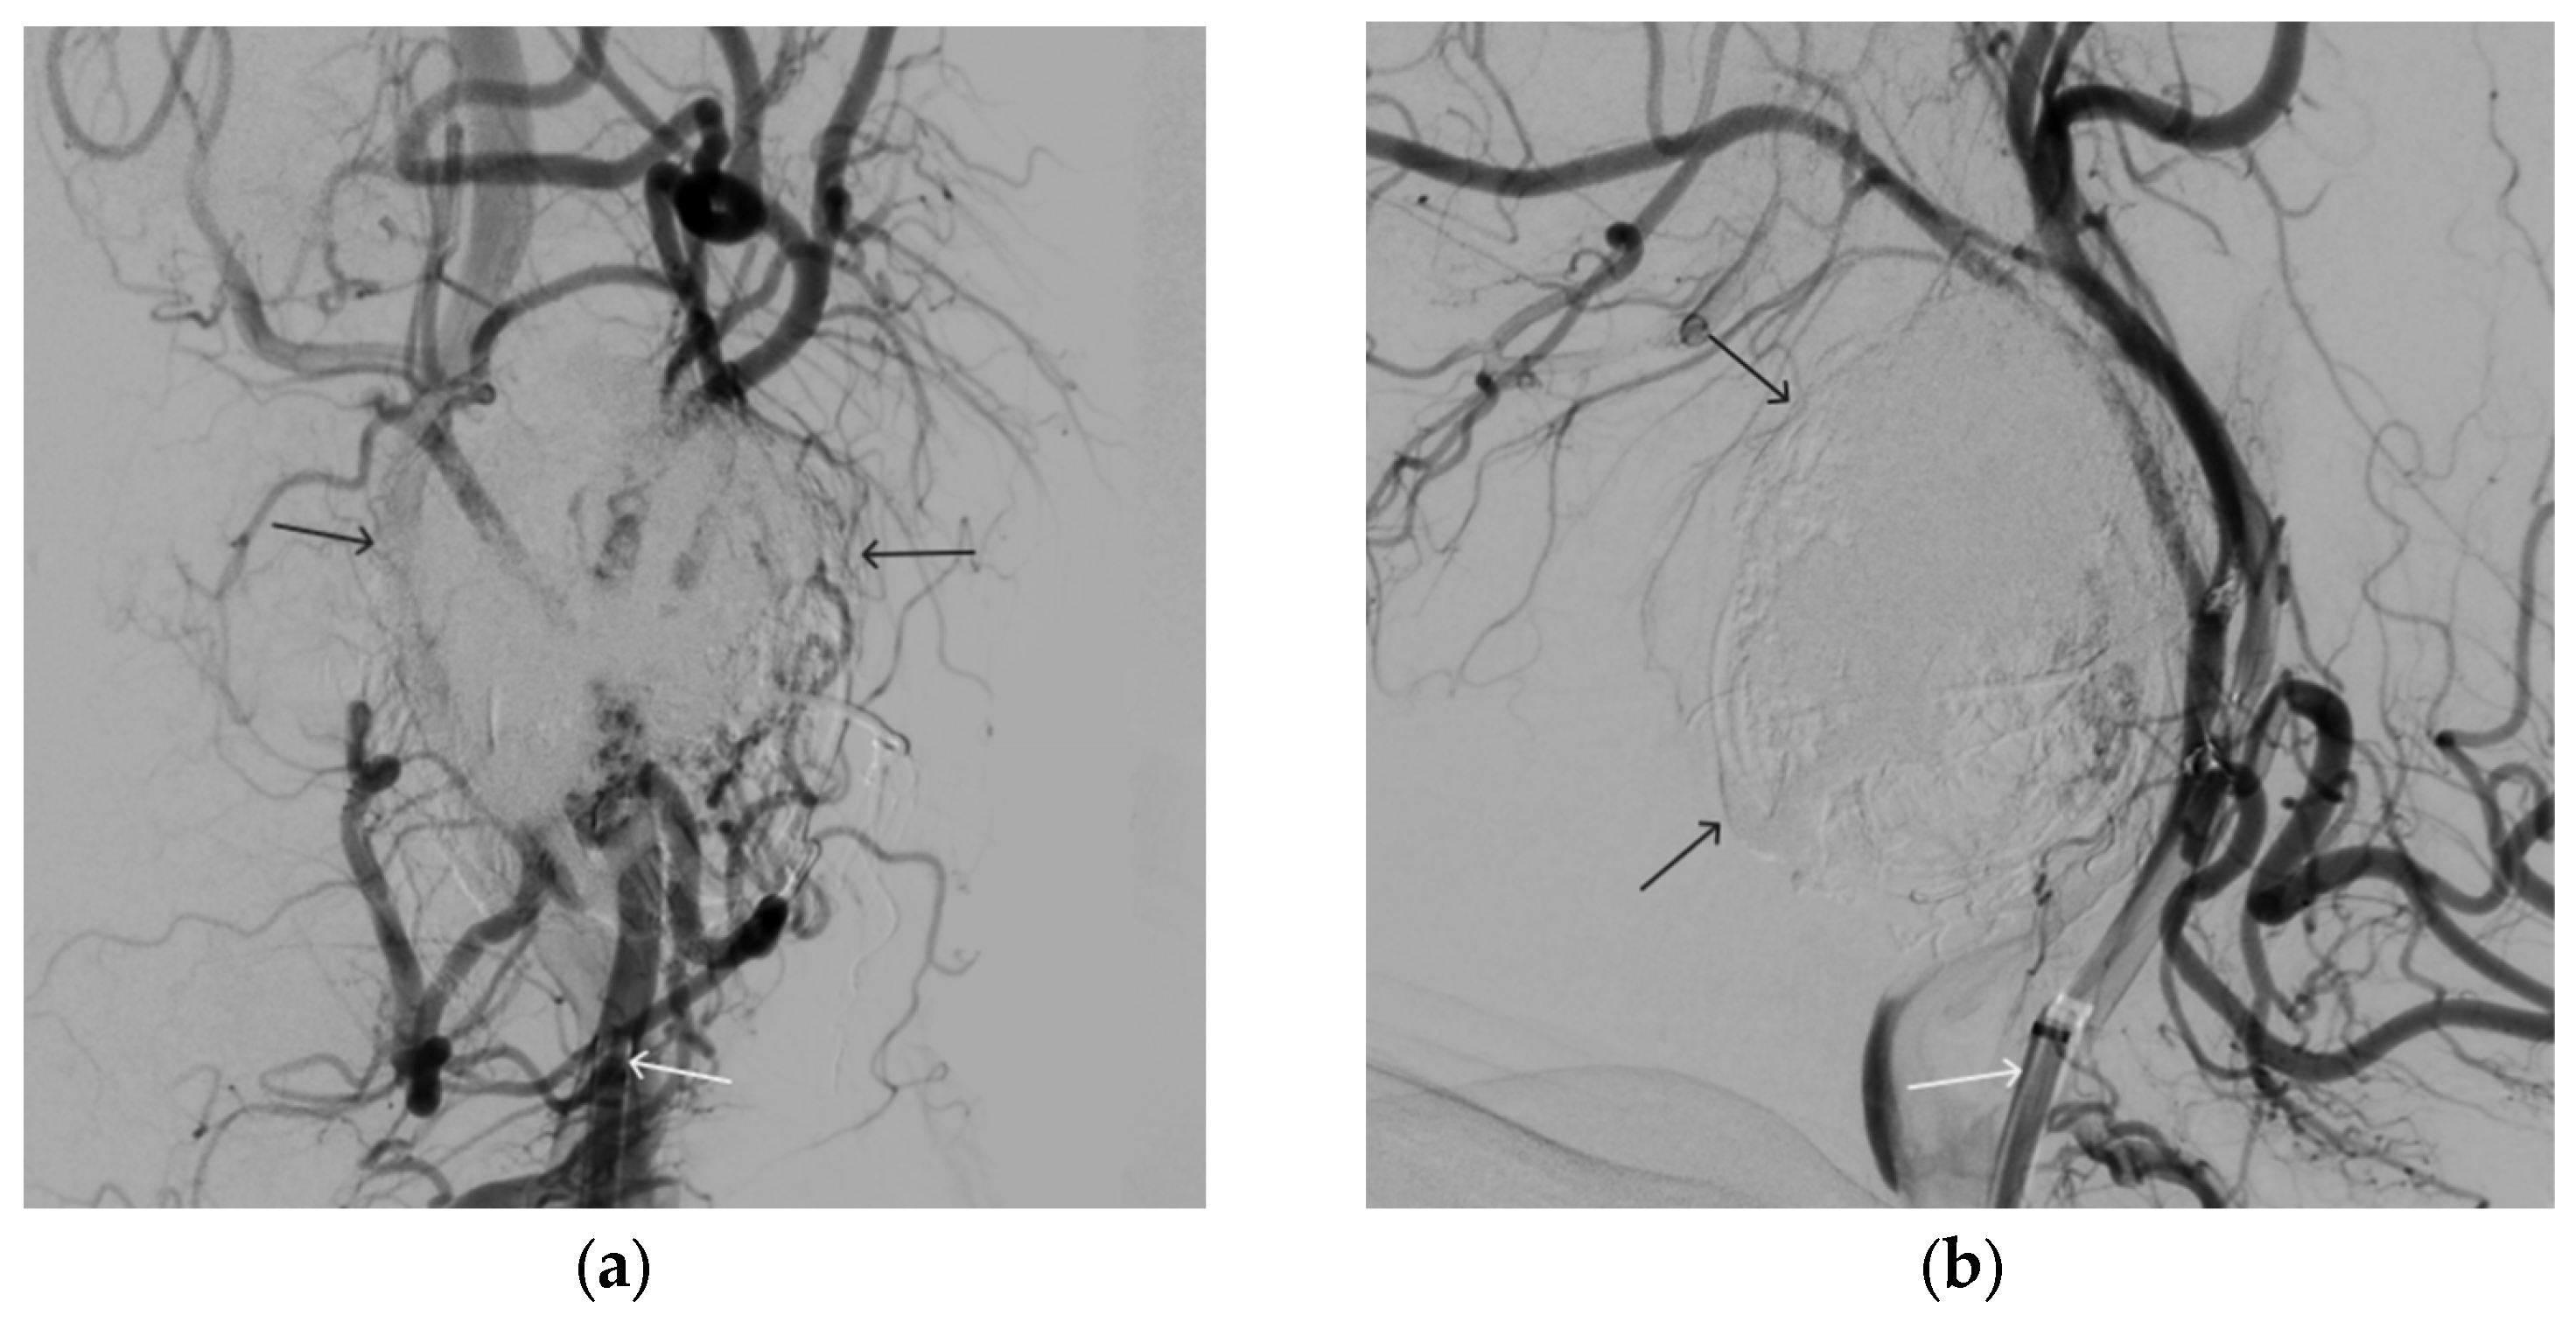

A 35-year-old male patient was admitted to the clinic with complaints of a cosmetic defect in the lower lip area. He has been ill since birth; 18 years ago he was diagnosed with AVM of the lower lip and microsurgical removal was performed. Over the past three years, the growth of formation has been noted. Angiography revealed a relapse of arteriovenous malformation with afferents from the left facial artery (Figure 3). In three years, he underwent several stages of treatment: endovascular embolization with gelatin sponge and embolization with pure ethanol, without effect. The patient underwent endovascular embolization of the AVM of the lower lip with 5 mL of non-adhesive composition ONYX18. Arteriovenous malformation was shut down totally (Figure 4, Figure 5 and Figure 6). The patient was directed to the next stage of surgical treatment—AVM removal by cosmetic surgeons (Figure 7). The mRs score at discharge was 1.

A 48-year-old male patient was admitted to the clinic with complaints of a subcutaneous volume formation in the lower jaw area on the left. Earlier, in another clinic, an attempt was made to embolize the AVM using microcoils. Angiography was performed; filling of the AVM of the soft tissues of the face in the area of the angle of the lower jaw on the left was noted. The presence of separable coils in the afferent from the previous operation was noted; however, the AVM was filled through the coils (Figure 8 and Figure 9). Total embolization of the AVM of the face soft tissues with 7.5 mL of non-adhesive composition ONYX18 was performed. Arteriovenous malformation was totally shut down (Figure 10). There were no complications. The mRs score at discharge was 0.

Figure 6. Digital subtraction angiography from the right and left facial arteries: (a) direct projection; (b) lateral projection (white arrows indicate catheters at the ostium of the facial arteries, black arrows indicate embolizate cast). The absence of AVM contrast is noted.

Figure 8. Digital subtraction angiography from the left external carotid artery, direct projection (white arrow indicates catheter in the left external carotid artery, black arrows indicate contrast AVM).

Figure 9. X-ray, direct projection (the white arrow indicates a microcatheter in the left external carotid artery, the black arrows indicate a complex of microcoils from the previous stage of embolization).

Figure 10. Digital subtraction angiography from the left external carotid artery, direct projection (white arrow indicates the left external carotid artery, black arrows indicate the boundaries of the filled AVM).